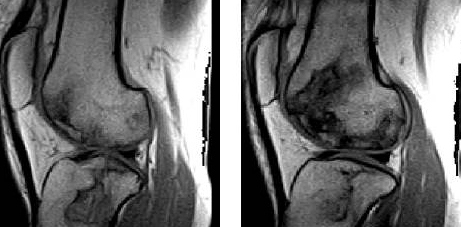

(4)病灶呈多发,形态不规则,并有融合趋势,呈典型“地图”样。

地图样改变,周围不规则线状样影包绕,关节软骨保持正常。邹月芬:骨梗死的影像学表现。

地图样改变,周围不规则线状样影包绕

地图样改变,周围不规则线状样影包绕,